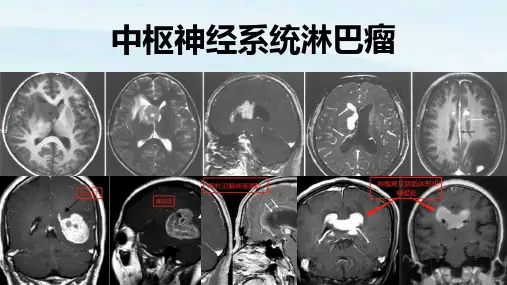

结果本组8例患者共14个病灶,其中4例为单发病灶,4例为多发病灶。

病灶部位包括额叶、颞叶、岛叶、枕叶、胼胝体、侧脑室周围脑白质、脑室室管膜及室管膜下、小脑蚓部,且多位于幕上,仅1个位于幕下。

MRI显示T1WI呈等或低信号、T2WI呈等或略高信号,仅1例病灶合并出血、2例有囊变,均未见钙化,瘤周均有水肿,增强扫描呈明显均匀强化。

结论原发性中枢神经系统淋巴瘤的MRI表现具有特征性,掌握其MRI特点有助于提高诊断的敏感性及准确性。